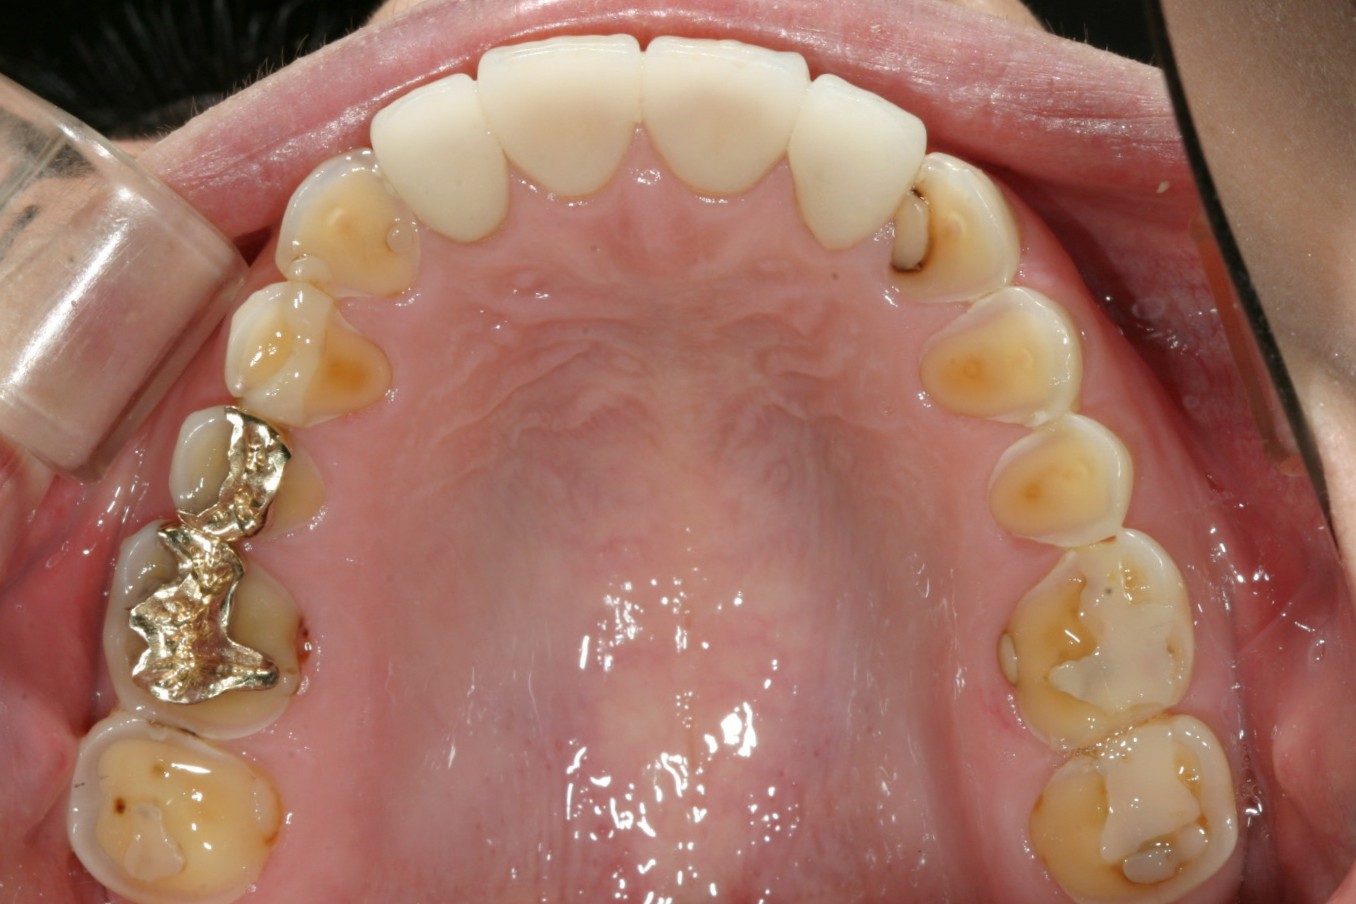

奥歯を見て下さ‼ 全体的にすごく摩耗して黄色い象牙質が向き出ています。